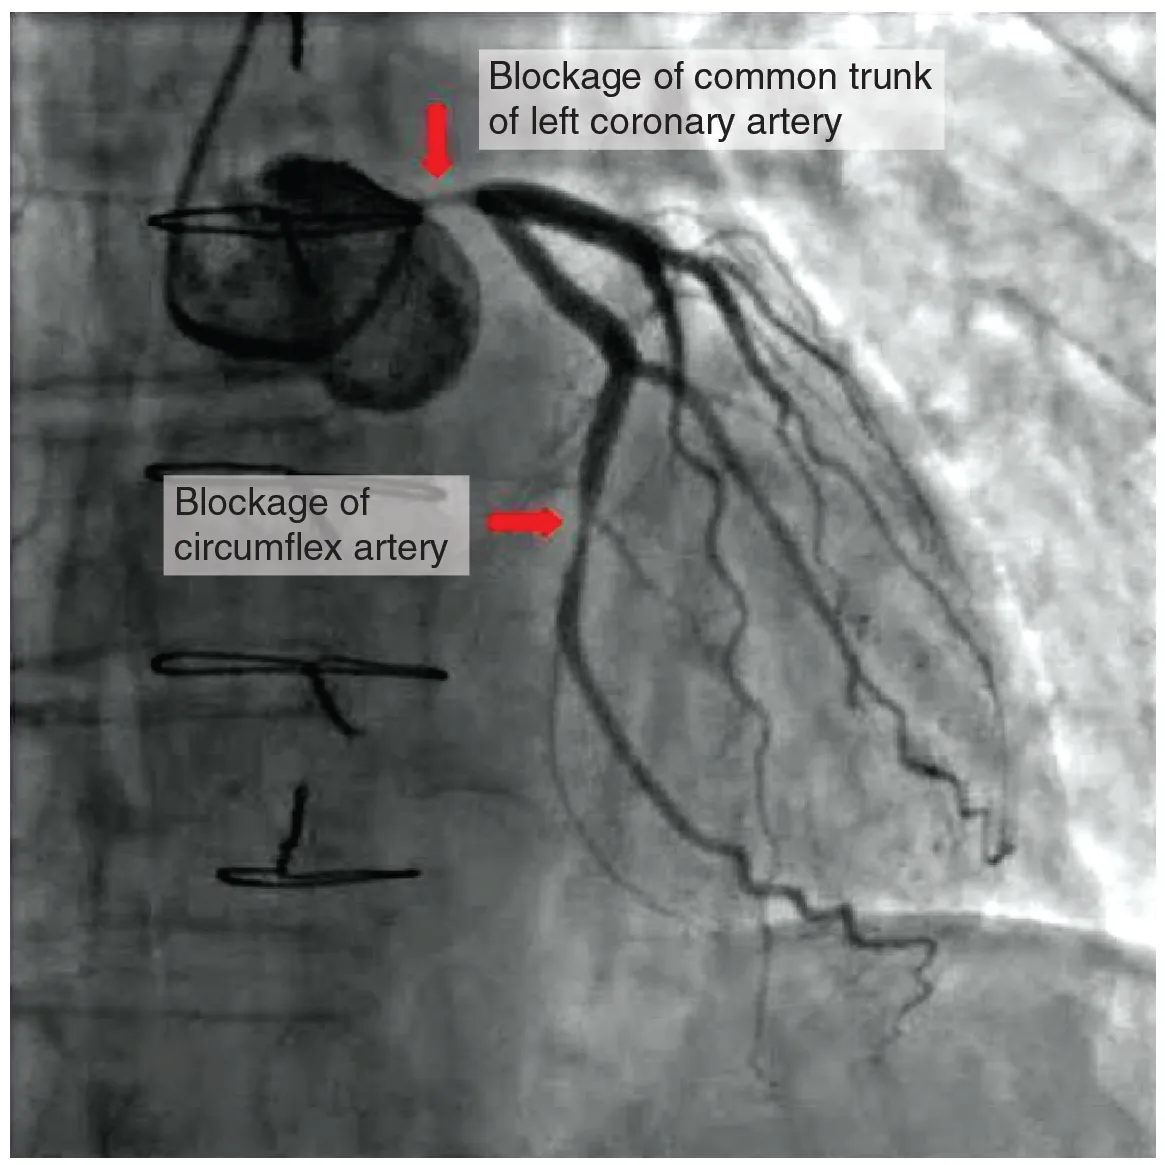

Coronary artery disease is the leading cause of death worldwide. It occurs when the buildup of plaque—a fatty material including cholesterol, connective tissue, white blood cells, and some smooth muscle cells—within the walls of the arteries obstructs the flow of blood and decreases the flexibility or compliance of the vessels. This condition is called atherosclerosis, a hardening of the arteries that involves the accumulation of plaque. As the coronary blood vessels become occluded, the flow of blood to the tissues will be restricted, a condition called ischemia that causes the cells to receive insufficient amounts of oxygen, called hypoxia. Figure 3.16 shows the blockage of coronary arteries highlighted by the injection of dye. Some individuals with coronary artery disease report pain radiating from the chest called angina pectoris, but others remain asymptomatic. If untreated, coronary artery disease can lead to MI or a heart attack.

The disease progresses slowly and often begins in children and can be seen as fatty “streaks” in the vessels. It then gradually progresses throughout life. Well-documented risk factors include smoking, family history, hypertension, obesity, diabetes, high alcohol consumption, lack of exercise, stress, and hyperlipidemia or high circulating levels of lipids in the blood. Treatments may include medication, changes to diet and exercise, angioplasty with a balloon catheter, insertion of a stent, or coronary bypass procedure.

Angioplasty is a procedure in which the occlusion is mechanically widened with a balloon. A specialized catheter with an expandable tip is inserted into a superficial vessel, normally in the leg, and then directed to the site of the occlusion. At this point, the balloon is inflated to compress the plaque material and to open the vessel to increase blood flow. Then, the balloon is deflated and retracted. A stent consisting of a specialized mesh is typically inserted at the site of occlusion to reinforce the weakened and damaged walls. Stent insertions have been routine in cardiology for more than 40 years.